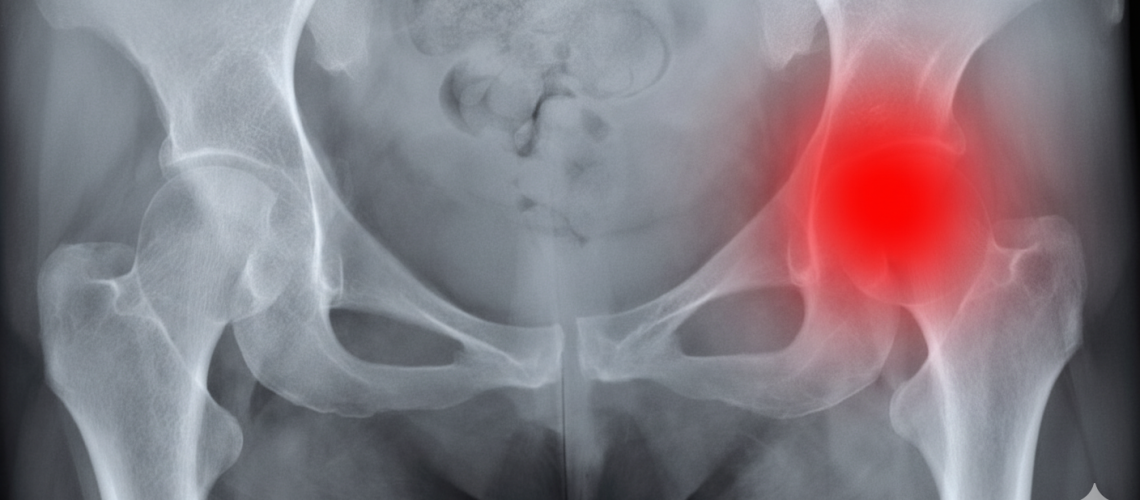

Os tumores localizados na região pélvica formam um grupo bastante diversificado de neoplasias que comprometem órgãos como o útero, ovários, bexiga e reto. Devido à complexidade da anatomia desta área e à proximidade com estruturas vitais, tratar esses tumores cirurgicamente requer uma abordagem envolvente e especializada de vários ramos médicos.

Enfrentar tumores na região pélvica envolve vários desafios significativos, como a execução de ressecções precisas para retirar completamente o tumor sem afetar funções essenciais. Devido à proximidade de nervos, vasos sanguíneos e outros órgãos, o procedimento torna-se delicado, potencializando os riscos de complicações tanto durante quanto após a operação. Adicionalmente, as variações na apresentação clínica e no estágio da doença pedem planos terapêuticos individualizados para cada paciente.